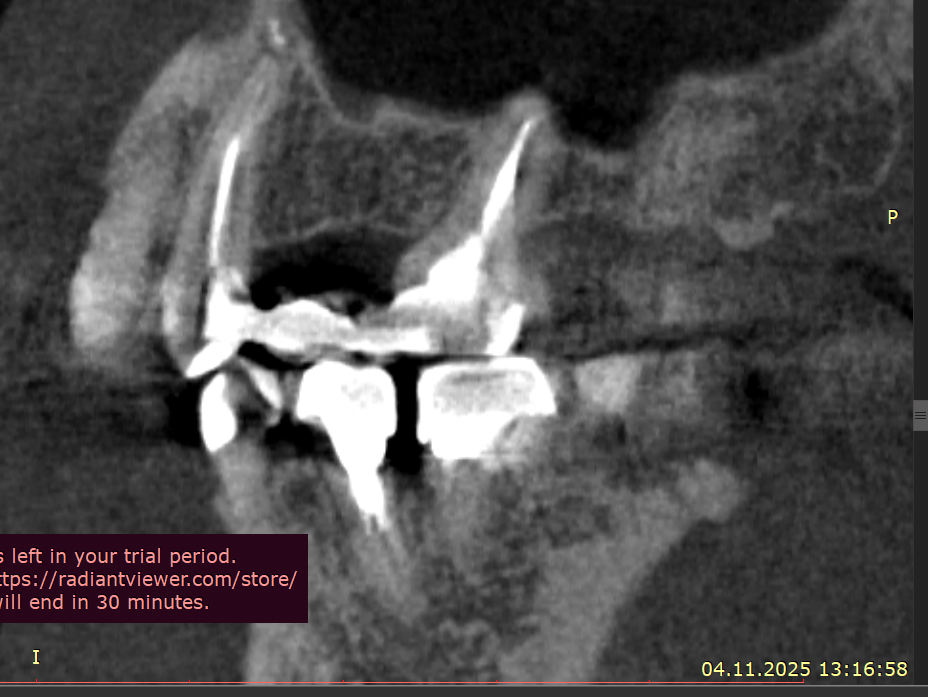

Добрый вечер Подскажите пожалуйста, вчера ел арахис, это очень редко бывает и мне такое противопоказано, и слышу один твёрдый попался немного, в момент когда накусил немного в области 4–5 зуба вверху справа, почувствовал боль, которая по сейчас сохраняется, боль чувствую именно в периодонте (к сожалению кто меня помнит с моей историей длительной я уже знаю как отличать боль по чувствительности, ту или иную), делал КЛКТ 3 недели, просто планово по поводу других зубов, посмотреть что и далее сохраняется положительная динамика после больших перенесённых периодонтитов, в вот посмотрел заодно на вот эти (открыл дайком) где вчера накусил, там нет и не было деструкции кости, зубы давно мертвые и нужно менять реставрации, зубы эти при надавливании пальцем не болят, жевать тоже не усиливается, просто ноющая периодонтальная боль извините за сленг, острой боли прям в момент накусывания арахиса тоже не было

Так же посоветуйте пожалуйста, как лучше поступить в случае 24-26, почти 2 года назад был большой периодонтит, киста пазухи. карман между 26\27, предварительно это удалось вылечить, уже 9 месяцев ничего там не болит, все спокойно, по кт медленно но есть положительная динамика, хотя все говорили удалять и только, возможно прям долгие годы эти зубы не простоят, но я хотел снять адегизивный, коронка, которая закрывает 25 отсутствующий, она крепится бабочкой между 26 и 24, и по хорошему коронки на 24,25,26 мост сделать, некоторые говорят имплант между 25, а 24 и 26 сделать просто реставрацию, я уже запутался, как лучше будет поступить ? Имплантат пока не хотел лишь по причине перенесенного в почти полтора года лонг ковида, это ужасный диагноз, в том виде в котором был у меня по крайней мере, и я хотел бы пока избежать более инвазивных процедур, хотя бы ближайшие пару лет, далее видно будет, но функционально и эстетически нужно наводить порядок, чем я и начал заниматься

Рентген сегодня сделал, трещины нет, но я слышал не на рентгене не на клкт часто трещины не видны, и лишь только под микроскопом